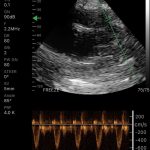

| Modo de escaneo | B, B/M, Color, PW |

Modos de escaneo: B, B/M, Color, PW

Mediciones: Longitud, área, velocidad, FC, S/D, LVIDd, LVIDs, SV, EF